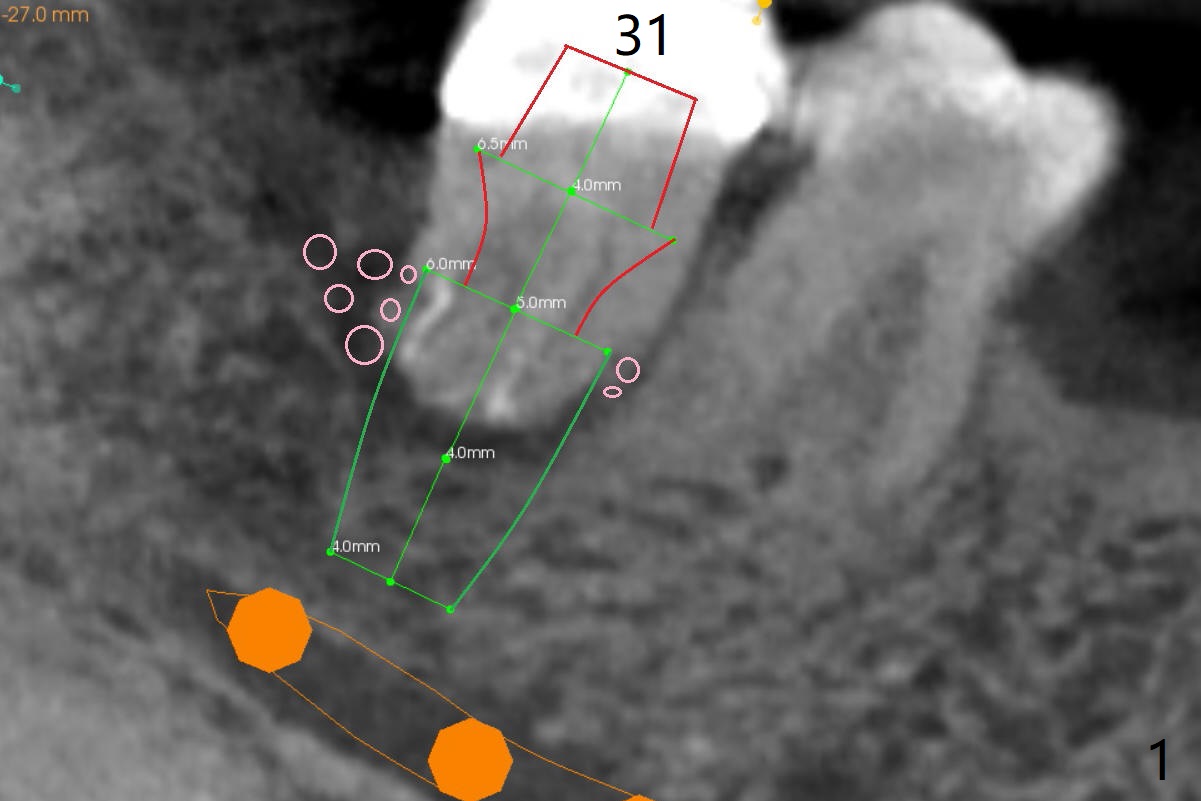

A 53-year-old man will return for #18 extraction and implant because of endo failure after the same treatment at #14 (Fig.1). It appears that the mesiolingual canal is missing for RCT (Fig.2 (coronal section at the mesial root)). Bony defect is buccodistal; try to place an implant as mesiolingual as possible (Fig.3 (axial section)). To reduce lingual (L) plate perforation and neuropathy (orange), the implant is expected to be 5-6x9 mm (Fig.4,5). Use 4 mm stopper from DIO Sinus Kit for osteotomy (Fig.1,4,5). If his vein is prominent, prepare PRF 1-2 tubes.